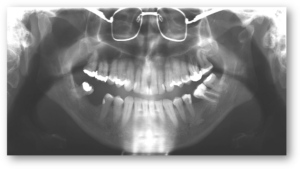

Knivskarpe røntgenbilleder

Knivskarpe røntgenbilleder – bedre billedkvalitet giver mere præcise diagnoser

Fif & tricks til udfordrende optagelser – perfekte bitewings, vanskelige 3ère og 8’ere, få alle rødderne med